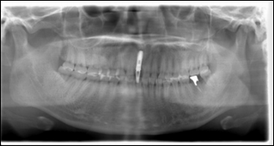

術前レントゲン写真

歯の根っこが割れているのが分かります。

インプラント埋入後のレントゲン写真